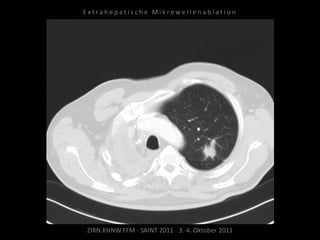

Patient: Männlich, 64 Jahre

Diagnose: Bronchial-Ca rechts, Z.n.

Pneumonektomie,

neu aufgetretene, solitäre, im Verlauf

progrediente Metastase im Oberlappen

links.

Ausgangsbildgebung:

CT vom 27.10.2010

Situation:

Nur eine Lunge und in dieser eine

(kleine) Metastase.